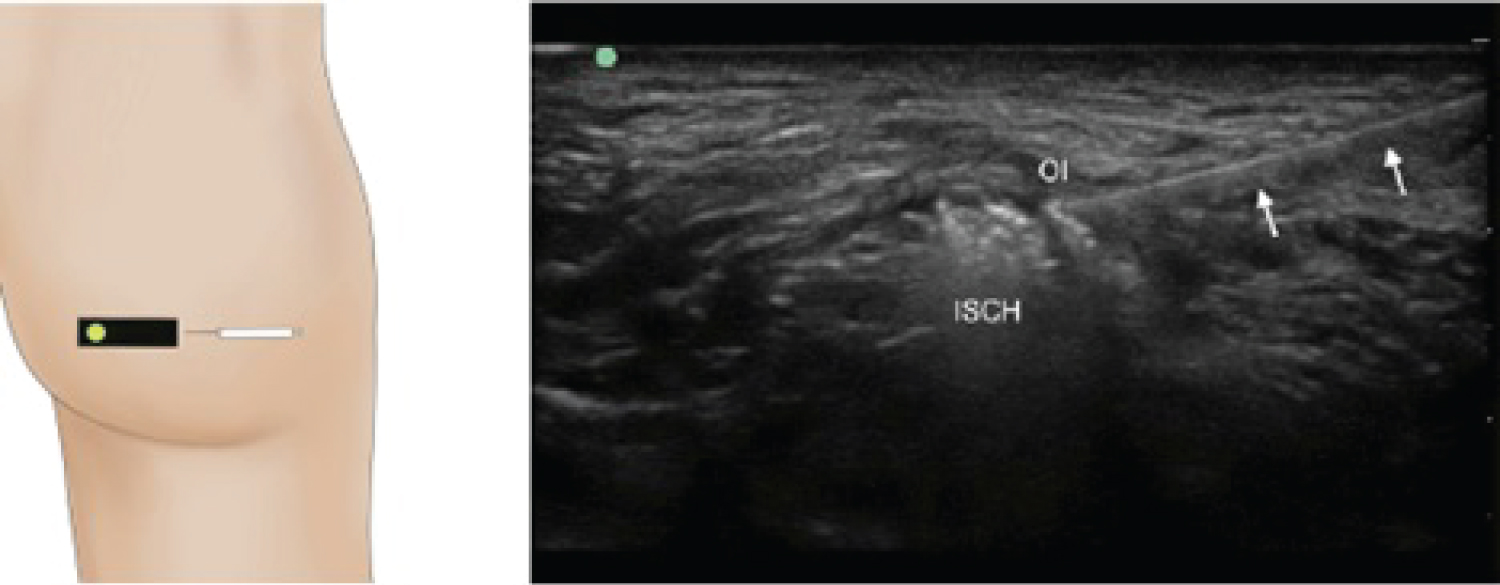

The point of maximal tenderness was palpated and then identified with ultrasound as the right OI (Figure 1). An US-guided lidocaine injection into the OI provided immediate and complete pain relief for 4 hours. As such, the right OI was then planned for BTA injection a few weeks later. Incobotulinum toxin was used at a concentration of 100 units per 1 mL in a 0.5 mL syringe. No further dilution of BTA was performed. A 27-gauge, 38 mm (1.5 inch) needle was used. US were used to identify the right OI. The needle was inserted in-plane with the US probe into the OI muscle belly in close proximity to the right ischial tuberosity. A total of 50 units were injected into one site. Over the next few days to weeks, she reported greater than 50 percent pain reduction, allowing her to sit in a chair and drive a car. Relief began to fade around 3 to 4 months with injections repeated each time with up to 95% pain relief.

Figure 1: A linear transducer was positioned horizontally over the point of maximal tenderness at the right ischial tuberosity. On long-axis view, the OI muscle was visualized crossing the ischium over the ischial spine and identified with passive internal and external rotation of the right leg. A 27 Gauge 1.5 inch needle directed in plane laterally to medially. Fifty units of BTA were injected with good spread noted within the muscle. (OI: Obturator internus, ISCH: Ischium, arrows: Needle). View Figure 1